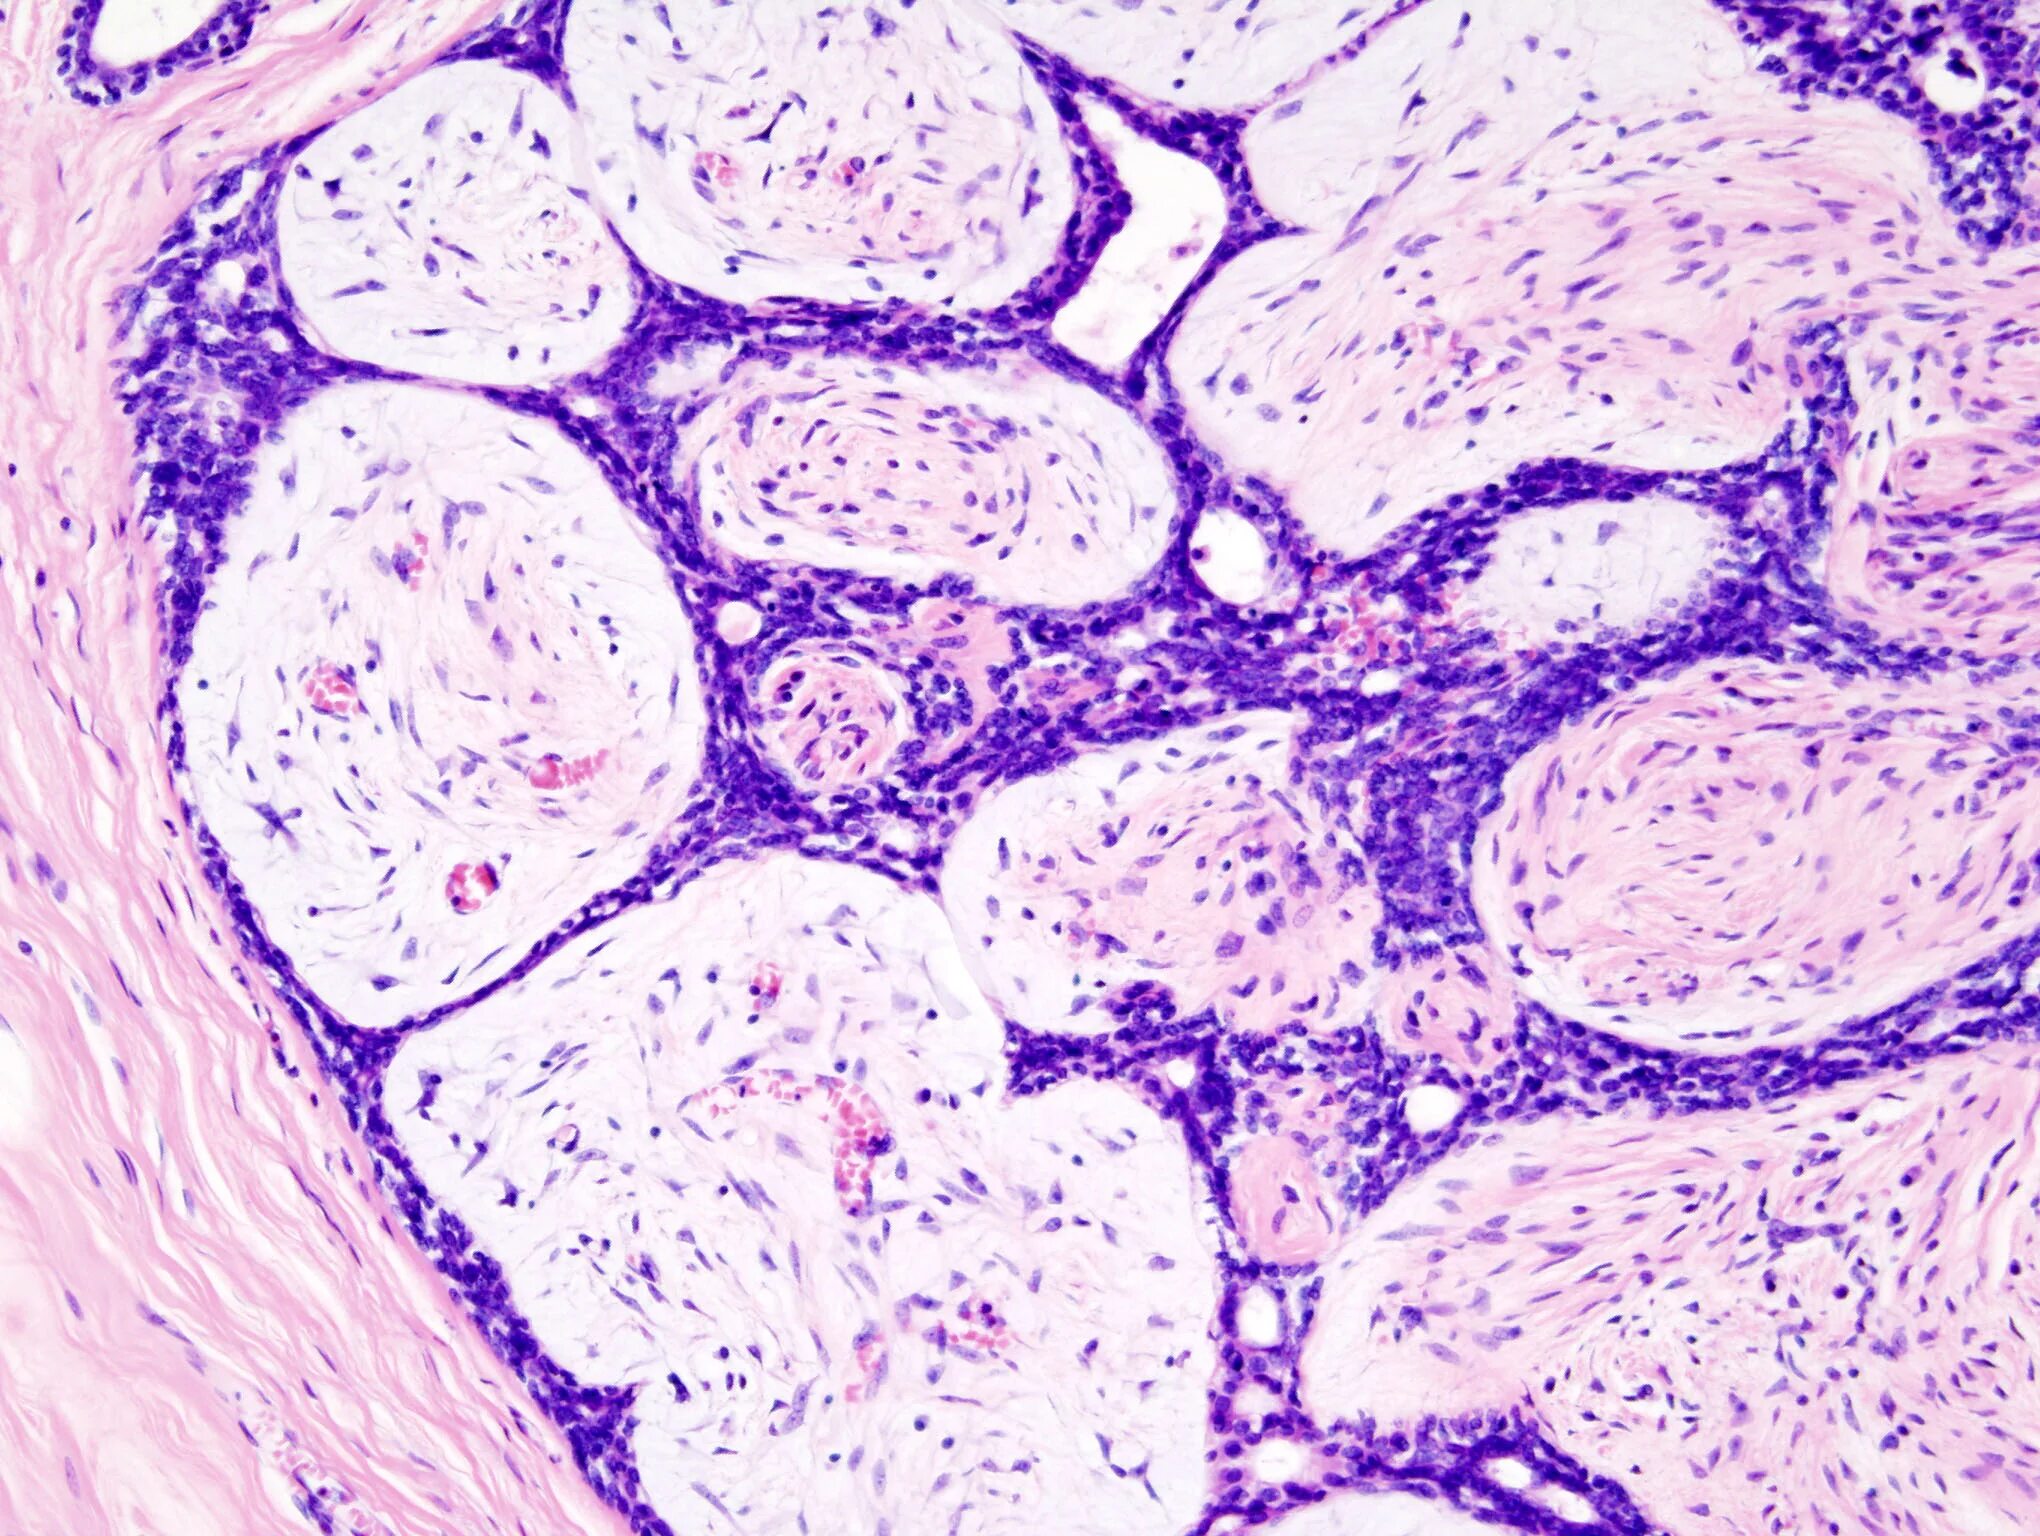

Опухоль с преобладанием стромы на ощупь